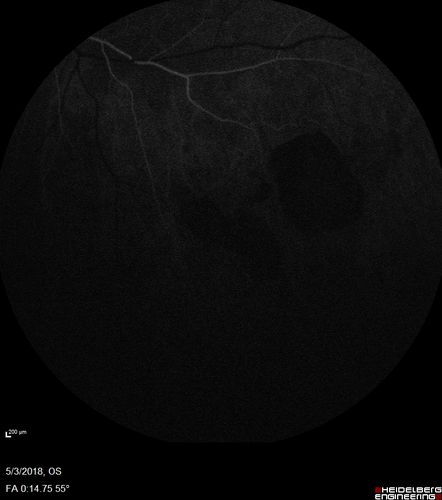

Coats' Disease -51 year old asymptomatic male

20/20 vision - had laser to non-perfusion because of proliferation.